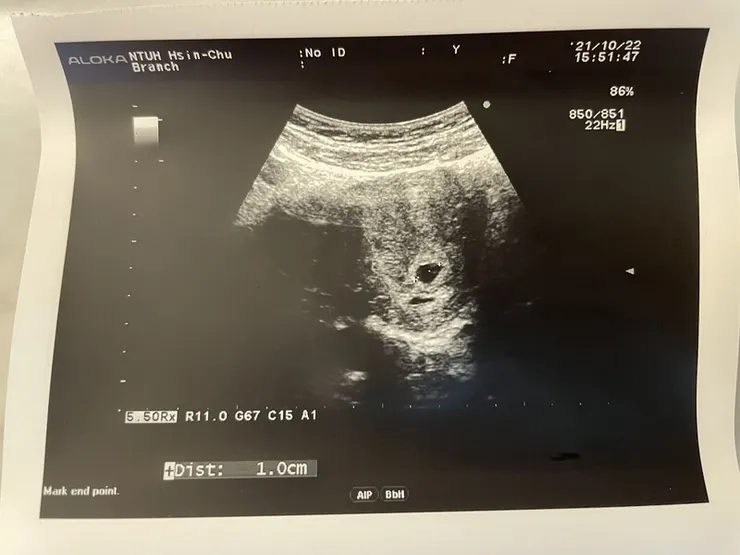

【第6周~胚胎長大】

胚囊現期約一天要大0.1cm,一周後回診有達到標準。Hen~~~棒!

但醫生卻說我的著床位置有點偏低,嚇得我們只能趕快取消隔天的台南遊QQ